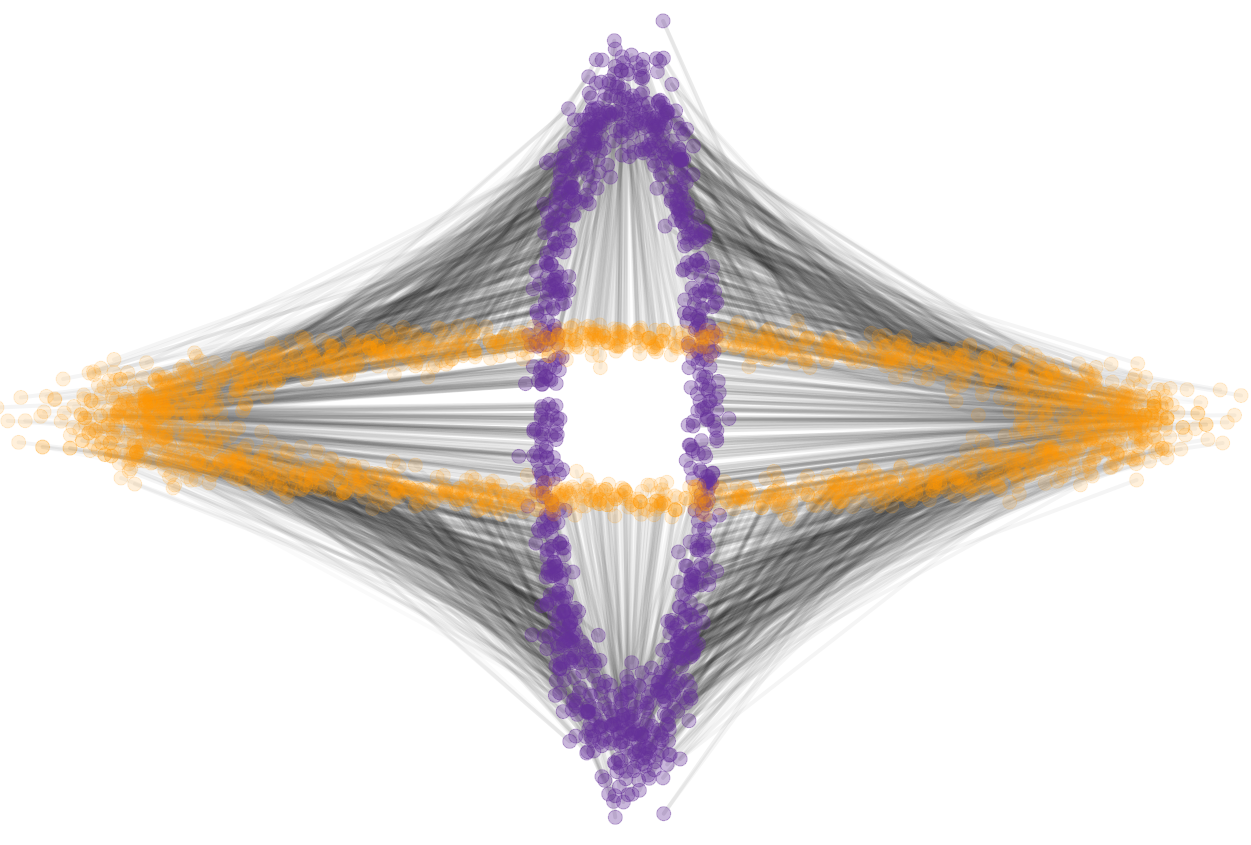

To solve for the optimal transport map between two 3D brain images we extract for each image a point cloud from the intensity volumes. Each point represents a voxel as a point in 3-dimensional space, the location of the voxel. The mass of the point is equal to the intensity value of the voxel, normalized to sum to one over all points. For illustration, Figure 9 shows a single slice extracted from the original volumes and optimal transport maps between the two slices. This 2D problem resulted in point set of approximately points.

|

|

| (a) | (b) |

|

|

| (c) | (d) |